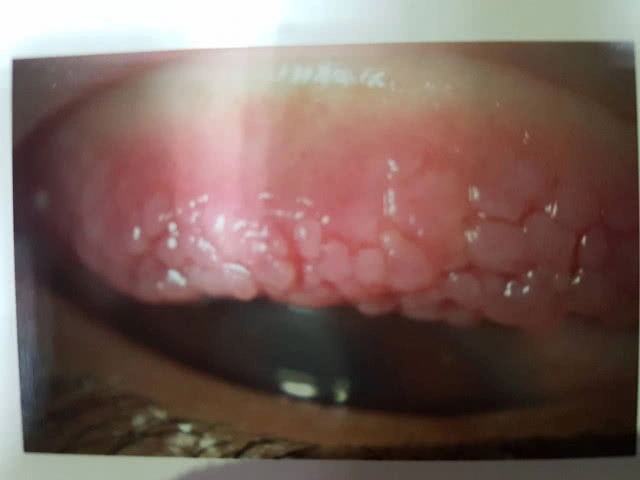

แพทย์หญิงสายจินต์ อิสีประดิฐ ผู้อำนวยการโรงพยาบาลเมตตาประชารักษ์ (วัดไร่ขิง) กล่าวเพิ่มเติมว่าโรคภูมิแพ้ขึ้นตาเกิดจากร่างกายมีปฏิกิริยาตอบสนองต่อสิ่งที่แพ้ โดยการอักเสบจะเกิดที่บริเวณเยื่อบุตาขาวเป็นหลัก สามารถเกิดจากหลายสาเหตุ ได้แก่ อาการภูมิแพ้ที่เกิดตามฤดูกาล มักเกิดจากละอองเกสรดอกไม้ ดอกหญ้า ซึ่งจะมีอาการตามฤดูกาลของสารกระตุ้นที่ทำให้เกิดภูมิแพ้ขึ้นตา ดังนั้นการรักษาและการใช้ยาจะเป็นแค่ช่วงที่มีอาการเท่านั้น สาเหตุอื่น ได้แก่ ไรฝุ่น อาหาร สารเคมี ขนสัตว์ เครื่องสำอาง ผู้ที่ใส่คอนแทคเลนส์เป็นระยะเวลานาน หรือทำความสะอาดคอนแทคเลนส์ไม่ถูกต้องหรืออาจแพ้สารเคมีในน้ำยาแช่คอนแทคเลนส์